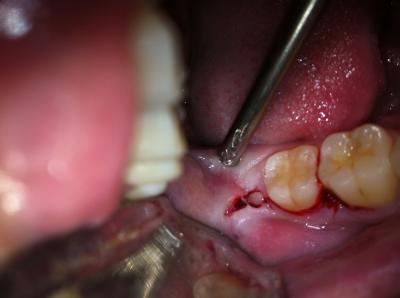

- Надрез десны, отслоение её от кости, осуществляется, чтобы добраться до удаляемого зуба и его корней.

-

Распиливание зубной единицы на несколько частей с последующим извлечением из мягкой ткани, выполняется с целью облегчения экстракции массивной восьмёрки.

В случае когда корни сломаны в процессе извлечения, их удаляют по отдельности.